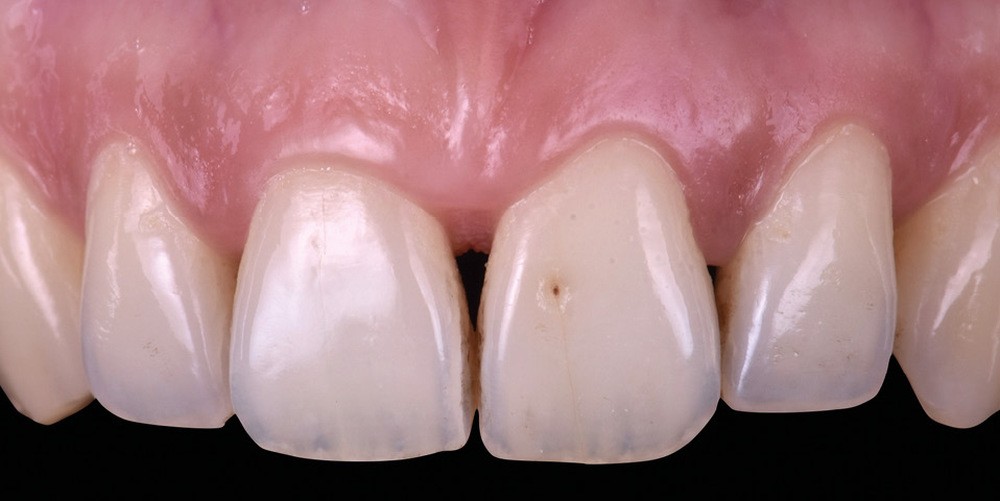

Si les techniques de reconstruction papillaire présentent des résultats non prédictibles, les facettes céramiques peuvent être une réponse fiable au problème des triangles noirs mais imposent une préparation plus marquée. En effet, pour obtenir un profil d’émergence adéquat et une bonne fermeture de l’espace interproximal, il faut préparer les surfaces de contact et venir chercher la ligne de transition palatine, obligeant à retirer une quantité de tissu sain non négligeable.

La fermeture des triangles noirs en technique directe avec des résines composites offre une alternative très favorable avec une approche non invasive, esthétique, un coût réduit et une possibilité de réintervention aisée. Plusieurs méthodes ont été proposées : réalisation à main levée sans matrice (à proscrire), avec bande de matrice transparente plate ou galbée, avec matrice postérieure customisée et utilisée verticalement… Il faut bien comprendre qu’aucun coin en bois ou plastique ne pourra être employé pour stabiliser cette matrice, car il empêcherait la création d’un profil d’émergence anatomique convexe en induisant une déformation concave de la matrice à sa base.